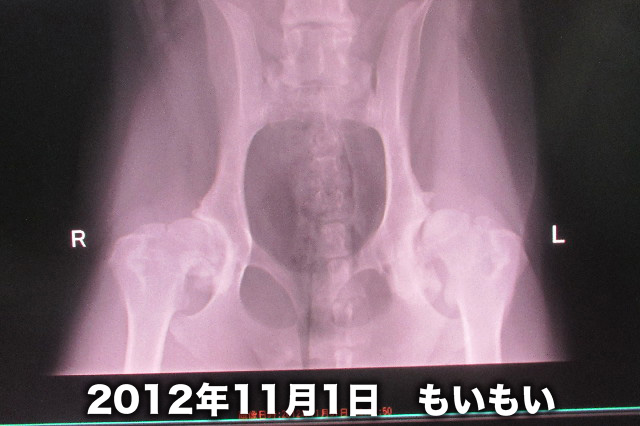

股関節はこんな。

夜間救急に保存の、2011年4月15日に下痢と嘔吐でかけこんだ時のレントゲンとほとんど変化なし。